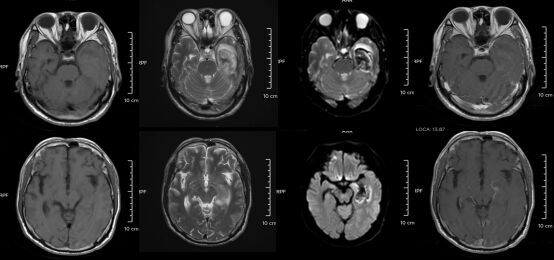

d2.jpg △某单纯疱疹病毒性脑炎患者的医学影像。图源:浙江大学医学院附属第二医院但如果拖延治疗,甚至会引发脑炎,可能出现癫痫、肢体偏瘫、尿潴留、认知功能障碍等严重后遗症,恢复时间长达3-6个月,甚至影响终身。